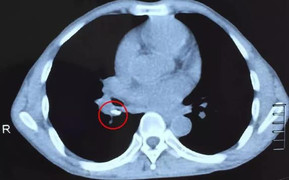

Cả 3 bé gái đều đột ngột hôn mê trước khi vào viện. Các bác sĩ chụp CT scan sọ phát hiện một búi dị dạng đường kính 2 x 3 cm ở thuỳ thái dương, thuỳ chẩm và thùy trán gây xuất huyết não – não thất.

Hình ảnh chụp não của một trong ba bé gái trước và sau phẫu thuật.